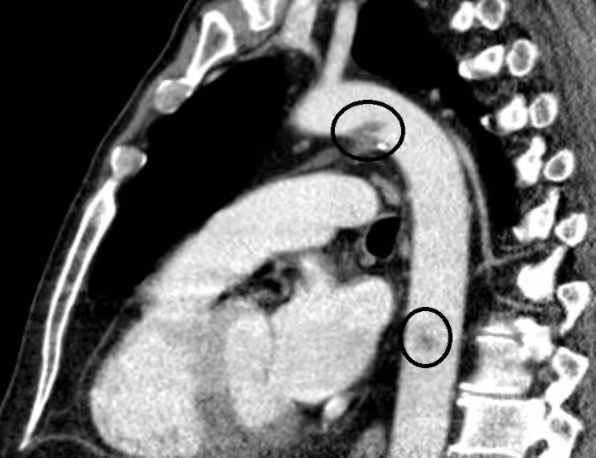

Patient with a Stanford type A aortic dissection

2021-03-08

in

Clinical Cases

Ventricular septal rupture as a complication of subacute myocardial infarction

2021-02-01